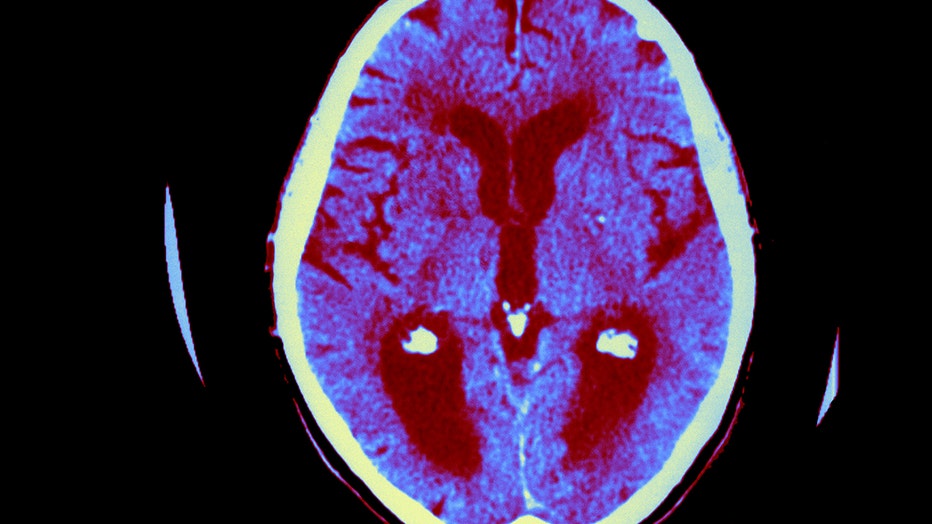

Axial Cut Away View. Median Portion Of Dilated Third Ventricle. Symettrical Dilation Of Intersections, Whereas The Cortical Horns Are Normal In Size. (Photo By BSIP/UIG Via Getty Images)